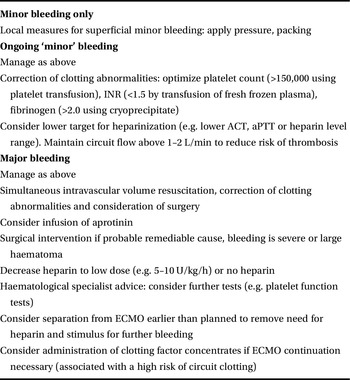

Management of bleeding in patients on ECMO involves optimization of coagulation using blood products, administration of drugs and surgical correction of the cause of bleeding. A suggested outline is given in Table 7.1.

Table 7.1 Management of bleeding in patients on ECMO involving optimization of coagulation using blood products, administration of drugs and surgical correction of the cause of bleeding

The first step is to rapidly assess the degree of haemorrhage. Major bleeding with haemodynamic compromise should prompt urgent intravascular volume resuscitation, ideally with cross-matched blood, and may require early surgical intervention.

Continued bleeding, despite optimization of platelet count, coagulation parameters and corrective surgery where indicated, should prompt further haematological input.

There is little trial evidence for the use of specific drug therapy in the management of bleeding in patients on ECMO, and support for particular agents is based on anecdotal reports.